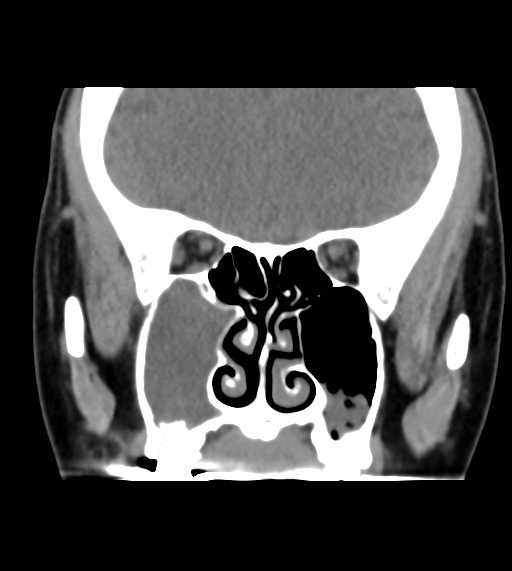

CT検査

その他の領域

その他

副鼻腔炎